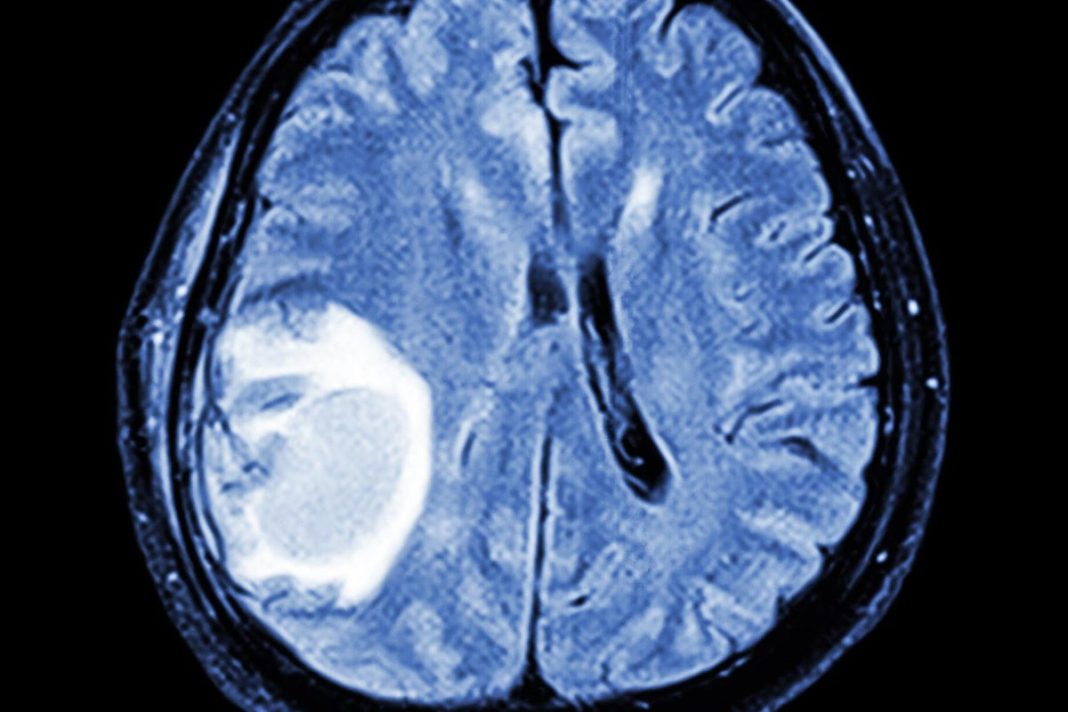

Close up illustration of a brain aneurysm

Close up illustration of a brain aneurysm (Alamy/pa) (Alamy/PA)

• Similarities between brain tumor cells and embryonic progenitor cells